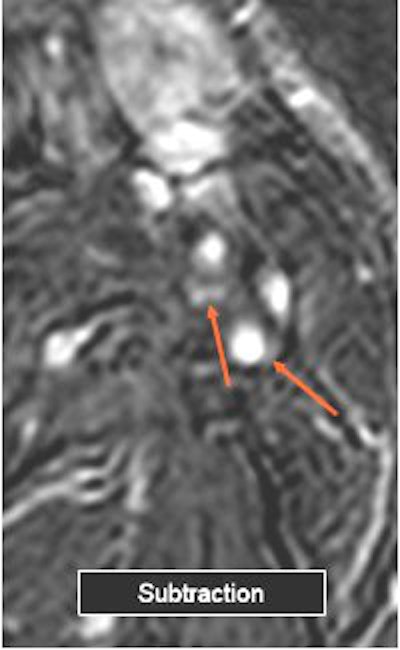

![]() |

| Above, the unenhanced image. Below, the enhanced image and the MRA showing plaque enhancement, which is more evident after electronic subtraction. All images courtesy of Dr. Francesco Sardanelli. |

"We can say that subtraction imaging is a useful tool to detect plaque enhancement," Flor said. "Plaque enhancement does not seem to correlate with the degree of stenosis as we see a large prevalence of moderate stenosis."